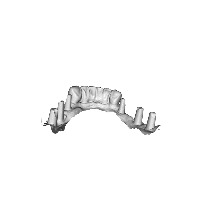

dental Computer Vision Project

Dental Health Education: Use the dental computer vision model in interactive educational tools or mobile apps for dentists, dental students, or patients, to help them understand different teeth types and their roles in oral functionality.

Dental Assessment and Monitoring: Integrate the model into dental software systems to help dentists quickly identify and assess teeth conditions such as tooth wear, dental occlusions, and potential prosthetic or orthodontic treatments.

Dental Equipment Design and Manufacturing: Apply the dental computer vision model in the design and development of dental implants, crowns, and other prosthetic devices by efficiently identifying the corresponding tooth classes and ensuring optimal compatibility with the tooth structure.